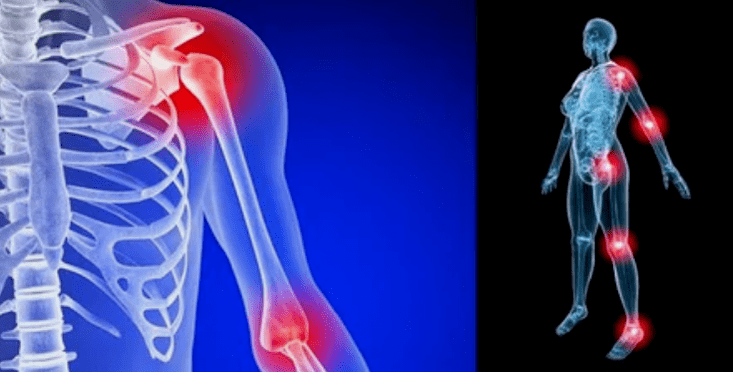

Le manifestazioni della malattia differiscono poco a seconda della localizzazione, più spesso i segni si riflettono sulle ginocchia, sulle articolazioni della spalla e dell'anca, a causa dell'elevato carico.

Le cause dell'artrosi delle articolazioni differiscono a seconda della forma di patologia. Deformando l'artrosi dell'articolazione del gomito, dell'articolazione della caviglia e dell'artrosi della spalla a volte si sviluppa senza cause evidenti, è possibile rilevarle con un medico, uno specialista in reumatologia. Se il problema non è stato preceduto da patologie visibili, la malattia è chiamata primaria. La forma secondaria di violazione è principalmente diagnosticata, può provocare vari stati.